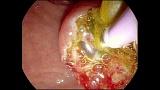

Здравствуйте. Пациентка, 32 года. Поступила на хирургическое отделение с диагнозом ЖКБ: холедохолитиаз. По данным МРТ: ЖКБ, множественные мелкие конкременты холедоха. При дуоденоскопии выявлено наличие вклиненного конкремента большого дуоденального сосочка. Выполнена прекатсфинктеротомия, получено 3 конкремента, диаметром около 0.4-0.5 см. Далее канюляция холедоха проволочным папиллотомом, выявлены многочисленные конкременты холедоха. Выполнена литоэкстракция ревизионным баллоном (на последнем фото окклюзионная холангиография - в просвете холедоха не конкременты, а пузырьки воздуха)).